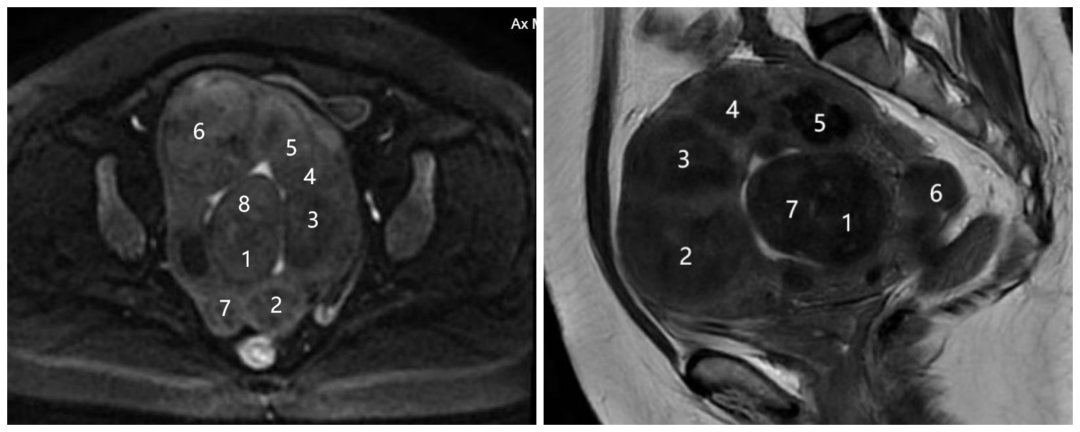

▲术前核磁图像,数字标注处为肌瘤